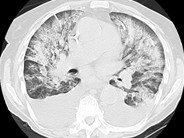

A 42-year-old male with history of myelodysplastic syndrome with progression to acute myeloid leukemia, which relapsed after induction therapy, was admitted to the hospital for initiation of Clofarabine therapy to reduce disease burden prior to bone marrow transplantation. On admission his white cell count (WBC) was 5200/uL with 77% blast cells and absolute neutrophil count(ANC) of 104/uL. Day 2, after chemotherapy, he was febrile and his WBC was 0/uL. He was empirically started on imipenem, daptomycin and amphotericin. Day 4, he developed erythematous lesion on abdomen(Fig.A) and right big toe(Fig.B). Computed tomography showed bibasilar pulmonary and hepatosplenic lesions (Fig C&D). The abdominal skin lesion developed a necrotic center with erythematous halo. All cultures were negative but KOH preparation from skin lesion showed nonseptate hyphae. Skin punch biopsy results were suggestive of mucormycosis. Patient was presumed to have disseminated mucormycosis. He failed to respond to dual antifungal therapy of high dose amphotericin and caspofungin. Disseminated mucormycosis is a rare and mostly fatal complication in severely immunocompromised patients.